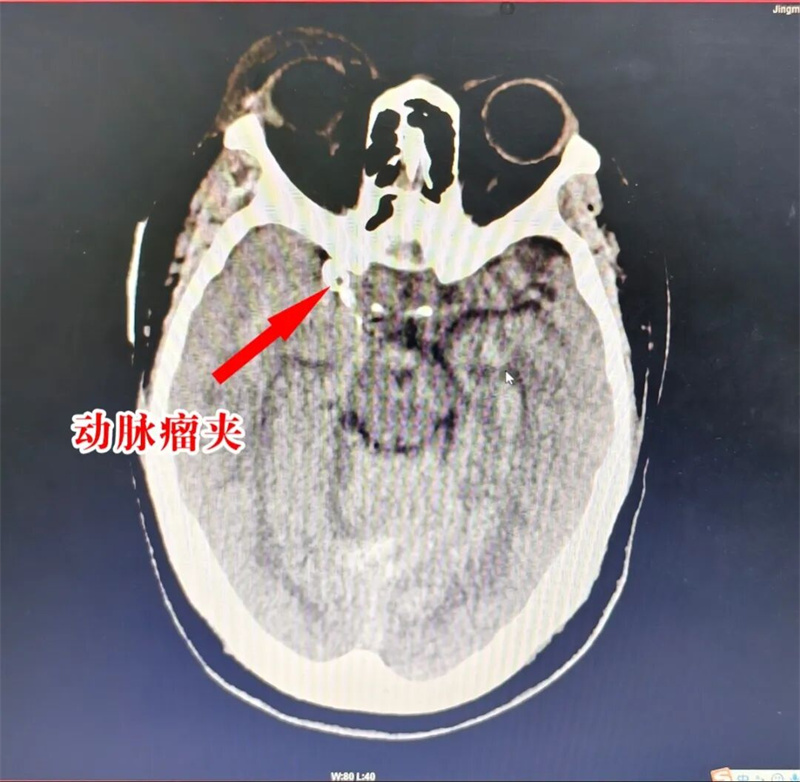

10月27日凌晨1时许,一声声呼救打破夜的沉寂……48岁的田女士(化名)被120急救车送到荆门市人民医院急诊科,她脸色苍白、神志模糊,双手紧紧抱着头。急诊医护一边询问病情——半小时前突发头晕、剧烈头痛、恶心呕吐,一边为她量血压——174/109m“查体高度怀疑脑血管问题!立即急查头颅CT。” 广泛蛛网膜下腔出血——最常见的病因就是颅内动脉瘤破裂。随后的头颈CTA(血管成像)提示右侧后交通动脉瘤、左侧后交通动脉瘤可能。

急诊CT提示:广泛蛛网膜下腔出血(脑室少许积血)

“患者CTA提示右侧后交通动脉瘤,直径约2.0mm×4.8mm,已经破裂出血。”傅楚华盯着屏幕上的影像缜密分析,“破裂的动脉瘤就像血管壁上漏气的气球,现在破口或只是被血凝块暂时堵住,高压血流随时可能冲开破口再次出血,第二次出血致死致残率将大大增加!”。